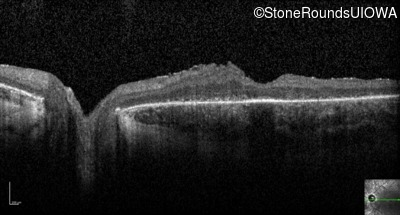

Optical Coherence Tomography - Right - 5/180 sc

Exemplar / OCT Stack